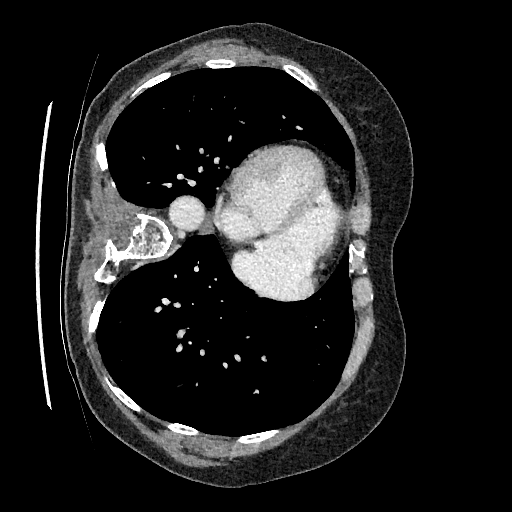

Sampling results

Original

Perturbed

Samples

Sampled